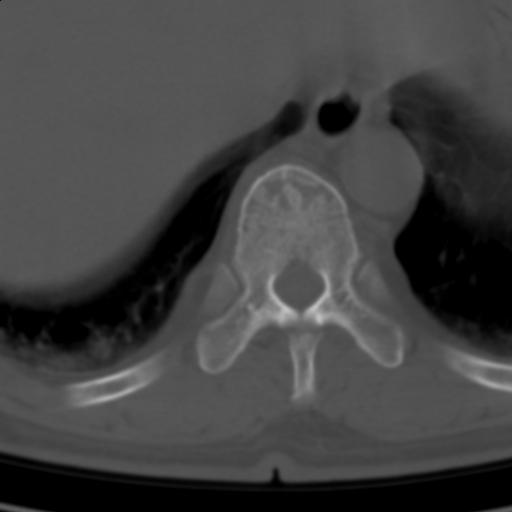

标题: CT25189:胸椎ct,请会诊!

既往食管癌,现行ct检查!

支持中上段食道癌,椎体轻度退变,必要时做ect。

中上段食道癌,椎体轻度退变。